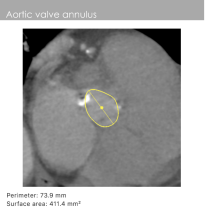

瓣环周长:73.9mm

左室流出道周长:78.8mm